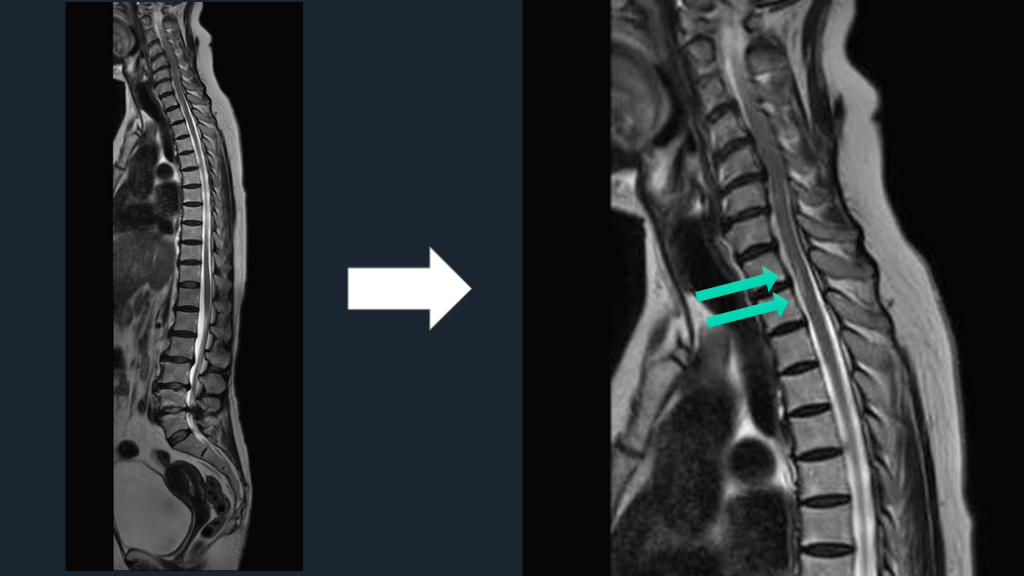

脊髄障害は、 悩むならwhole spine MRI 矢状断をとっておく。 TIPS

CASE 70歳女性例。突発発症の下肢対麻痺である。 先ほどのアイデアのごとく、4つの鑑別をまずは挙げる。 そして、MRIではどこを撮るのか?は正直、難しい。 正直、かっこつけずに、whole spine MRIでよいと思う。

脊髄障害の初手はwhole spineでよい。 脊髄緊急疾患でのWhole spine-MRIは推奨。 ER脊髄障害S/Oで、約半数の症例の脊髄緊急疾患診断に有用だった。 特に、外傷、麻痺、および排便/排尿症状患者で価値ある可能性 解説 Curr Probl Diagn Radiol. 2021;50:637-645. Handb Clin Neurol. 2017:140:319-335.

脊髄障害の初手はwhole spineでよい。 脊髄障害の高位診断は正直難しい。 症状の高位と実際の脊髄障害の高位は異なる。 実際の障害高位は、症状の高位よりも、より上にある。 対麻痺なら、腰髄レベルよりもより高位でどこでもあり。 腰髄レベルMRIのみ施行なら空振りリスクある。 それなら、WS-MRIの撮影でもよかろう。 解説